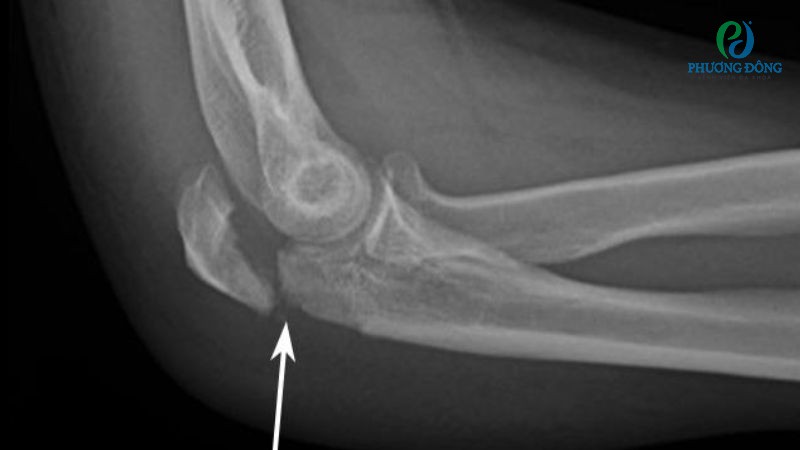

Hầu hết các trường hợp rạn xương khuỷu tay được chỉ định đeo nẹp hoặc bó bột cố định trong 3 - 6 tuần. Sau thời gian này người bệnh có thể luyện tập vận động nhẹ nhàng, tập phục hồi chức năng để trở lại sinh hoạt thường ngày.

Rạn xương khuỷu tay thường được bó bột cố định trong 3 - 6 tuần